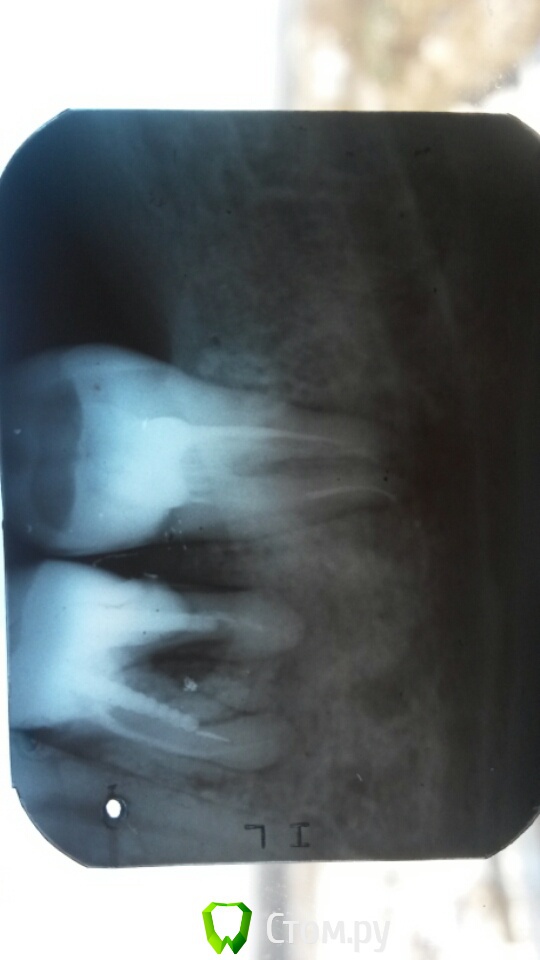

Галла Опубликовано 11 декабря, 2013 Автор Поделиться Опубликовано 11 декабря, 2013 Это свищ (выход гноя). Причина в зубе. Зуб удалять Д.д! А альтернативы никакой? Жалко всё таки лишатся своего родного. Зуб на снимке совсем плохой и не подлежит перелечиванию???? Ссылка на комментарий

Мартовский Опубликовано 11 декабря, 2013 Поделиться Опубликовано 11 декабря, 2013 Д.д! А альтернативы никакой? Жалко всё таки лишатся своего родного. Зуб на снимке совсем плохой и не подлежит перелечиванию???? Не подлежит. Чем быстрее вы эту бомбу уберете, тем лучше 2 Ссылка на комментарий